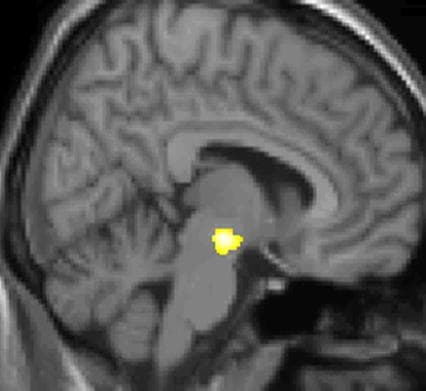

Voxel-based morphometry is a computational approach to neuroanatomy that measures differences in local concentrations of brain tissue, through a voxel-wise comparison of multiple brain images. In traditional morphometry, volume of the whole brain or its subparts is measured by drawing regions of interest (ROIs) on images from brain scanning and calculating the volume enclosed. However, this is time consuming and can only provide measures of rather large areas. Smaller differences in volume may be overlooked. The value of VBM is that it allows for comprehensive measurement of differences, not just in specific structures, but throughout the entire brain. VBM every brain to a template, which gets rid of most of the large differences in brain anatomy among people. Then the brain images are smoothed so that each voxel represents the average of itself and its neighbors. Finally, the image volume is compared across brains at every voxel. However, VBM can be sensitive to various artifacts, which include misalignment of brain structures, misclassification of tissue types, differences in folding patterns and in cortical thickness. All these may confound the statistical analysis and either decrease the sensitivity to true volumetric effects, or increase the chance of false positives. For the cerebral cortex, it has been shown that volume differences identified with VBM may reflect mostly differences in surface area of the cortex, than in cortical thickness. Over the past two decades, hundreds of studies have shed light on the neuroanatomical structural correlates of neurological and psychiatric disorders. Many of these studies were performed using voxel-based morphometry (VBM), a whole-brain technique for characterizing between groups' regional volume and tissue concentration differences from structural magnetic resonance imaging (MRI) scans. One of the first VBM studies and one that came to attention in mainstream media was a study on the hippocampus brain structure of London taxicab drivers.